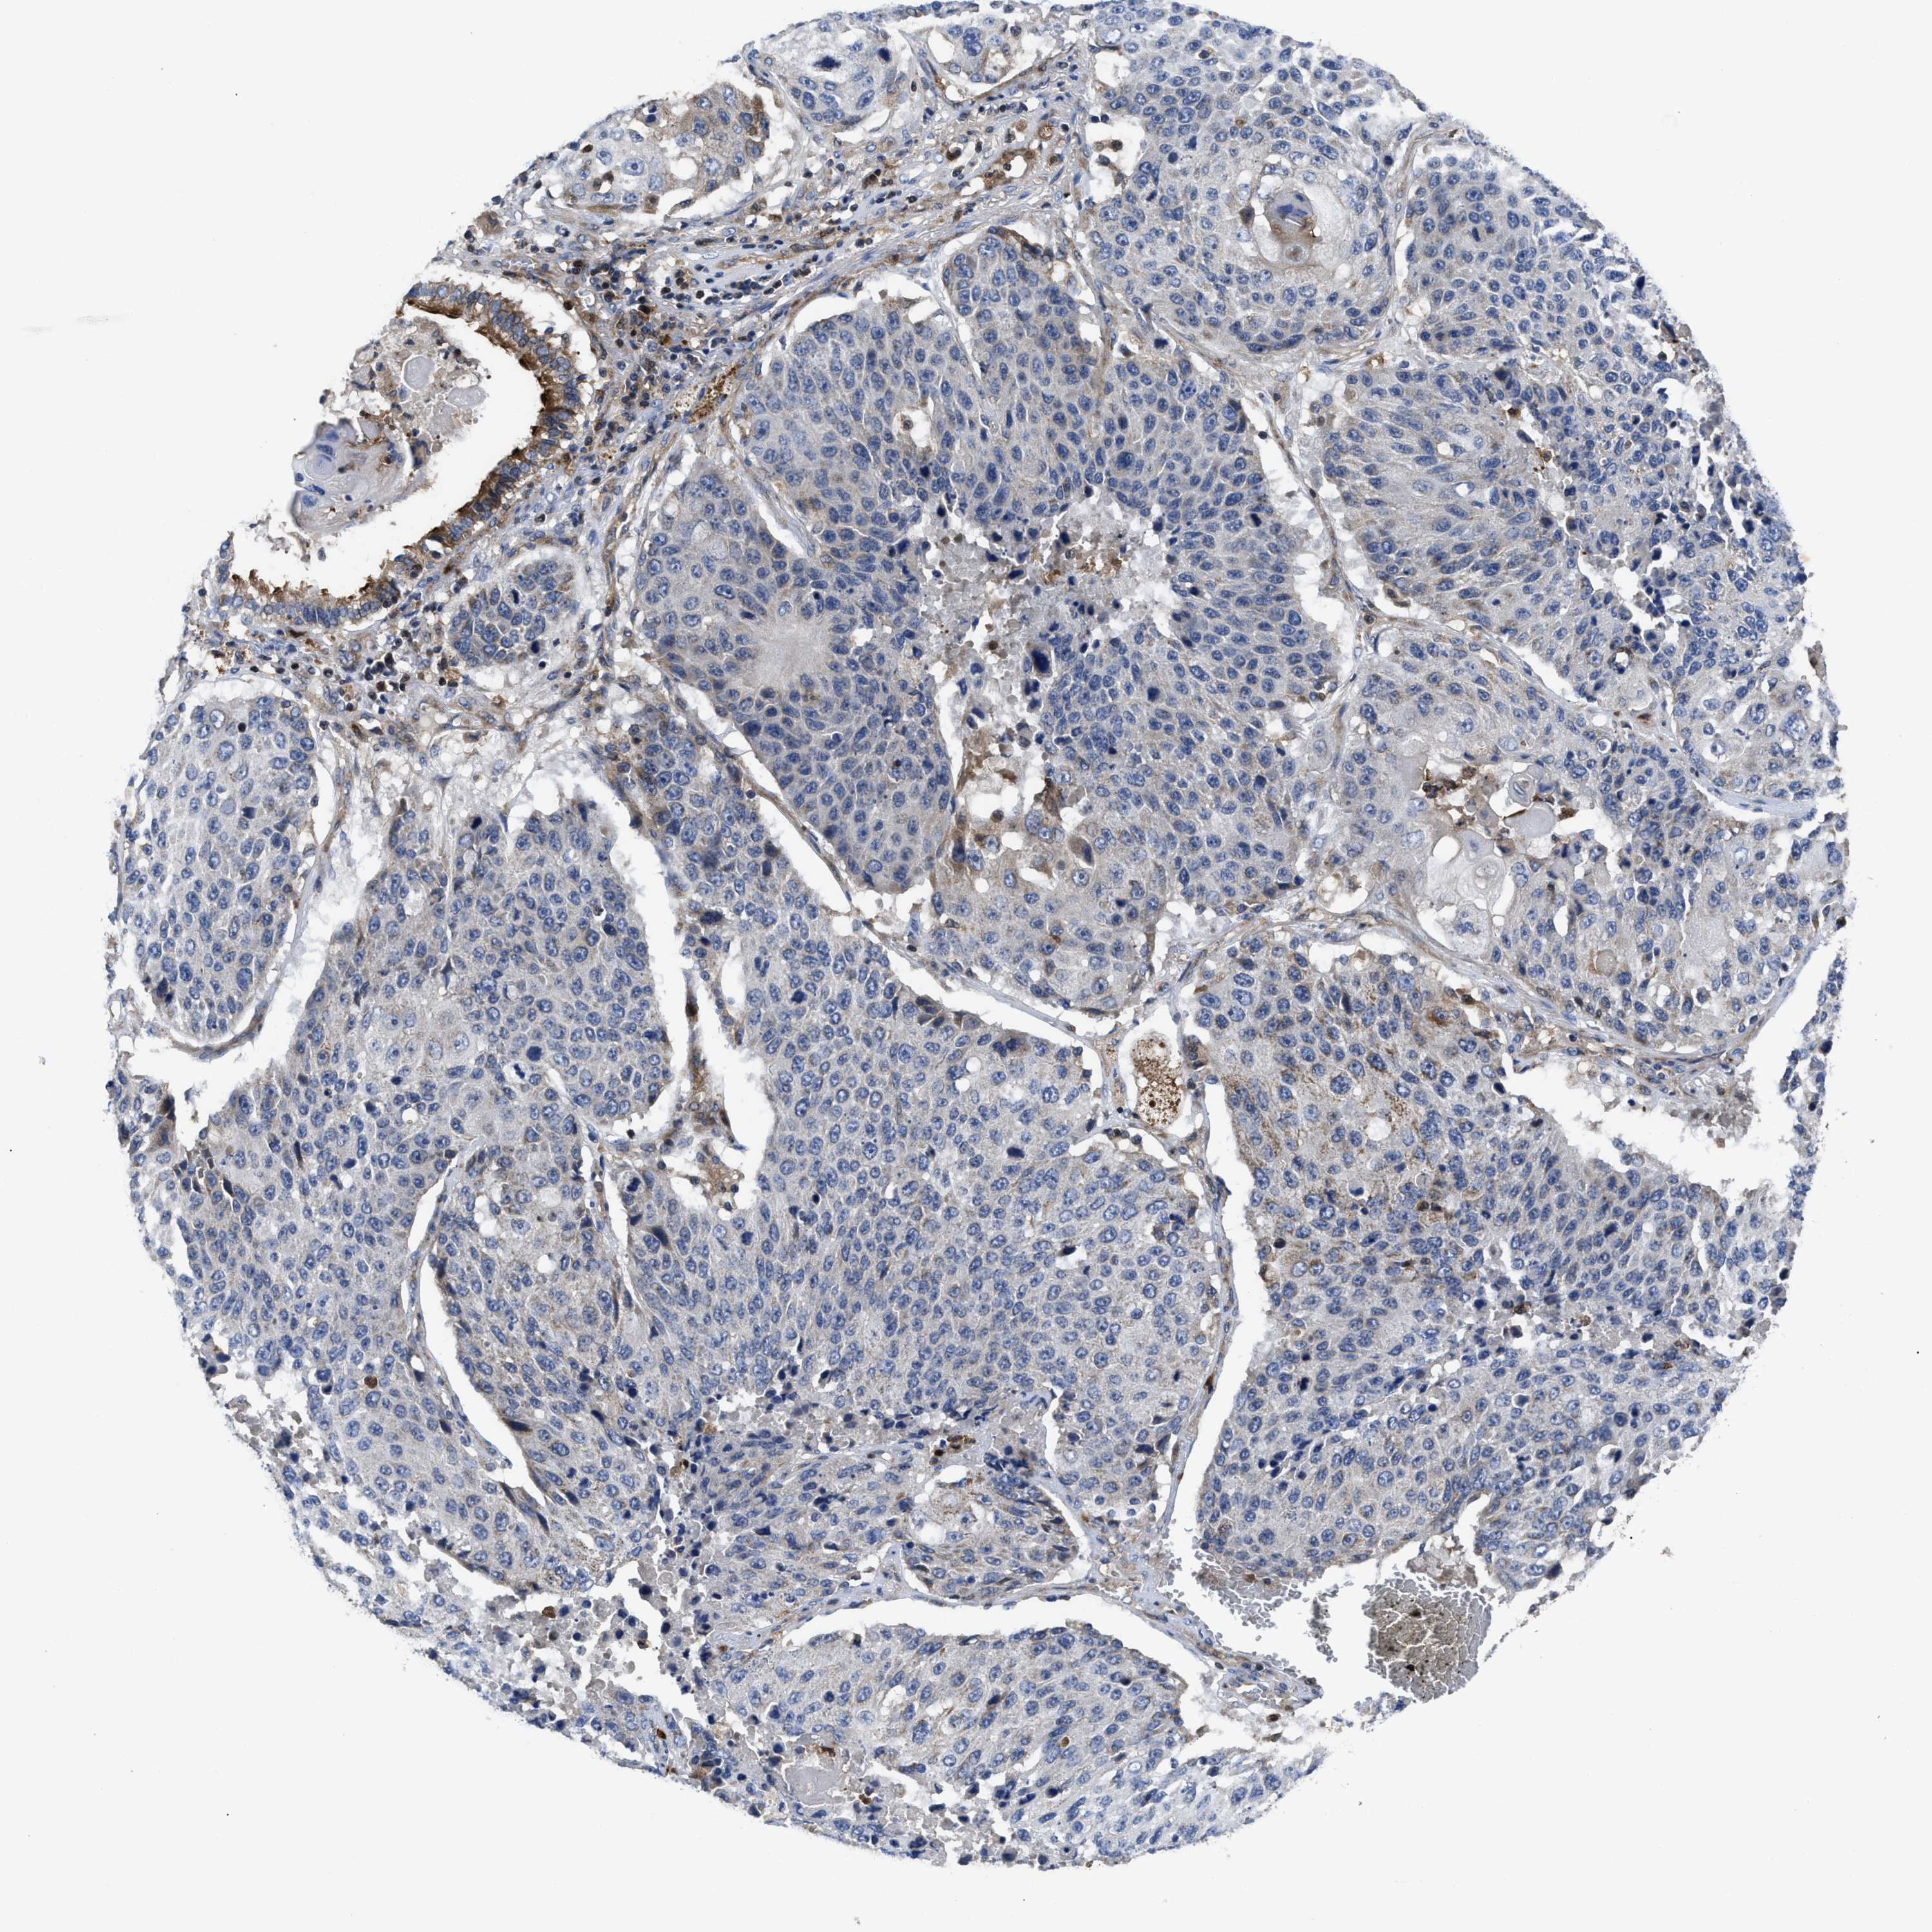

LUNG SQUAMOUS CELL CARCINOMA (TCGA) - Interactive survival scatter ploti

The Survival Scatter plot shows the clinical status (i.e. dead or alive) for all individuals in the patient cohort, based on the same data that underlies the corresponding Kaplan-Meier plots. Patients that are alive at last time for follow-up are shown in blue and patients who have died during the study are shown in red.

The x-axis shows the expression levels (FPKM) of the investigated gene in the tumor tissue at the time of diagnosis. The y-axis shows the follow-up time after diagnosis (years). Both axes are complimented with kernel density curves demonstrating the data density over the axes. The top density plot shows the expression levels (FPKM) distribution among dead (red) and alive patients (blue). The right density plot shows the data density of the survived years of dead patients with high and low expression levels respectively, stratified using the cutoff indicated by the vertical dashed line through the Survival Scatter plot. This cutoff is automatically defined based on the FPKM cutoff that minimizes the p-score. The cutoff can be changed by dragging the vertical line or by entering a cutoff value in the square labeled "Current cut-off".

Under the Survival Scatter plot the p-score landscape (black curve; left axis) is shown together with dead median separation (red curve; right axis). Dead median separation is the difference in median mRNA expression between patients who have died with high and low expression, respectively. It is calculated as follows: median FPKM expression of dead patients with high expression - median FPKM expression of dead patients with low expression. This is intended to aid the user in visually exploring custom cutoffs and the associated p-scores and dead median separation.

Individual patient data is displayed and can be filtered by clicking on one or more of the category buttons on the top of the page. Categories describing expression level and patient information include: high, low, alive, dead, female, male and tumor stages. The scale of the x-axis can be toggled between linear and log-scale by clicking on the "x log" button. Mouse-over function shows TCGA ID, patient information and mRNA expression (FPKM) for each patient.

& Survival analysisi

Kaplan-Meier plots summarize results from analysis of correlation between mRNA expression level and patient survival. Patients were divided based on level of expression into one of the two groups "low" (under cut off) or "high" (over cut off). X-axis shows time for survival (years) and y-axis shows the probability of survival, where 1.0 corresponds to 100 percent.

YBEY is not prognostic in Lung Squamous Cell Carcinoma (TCGA)

Stage:

: 9.45